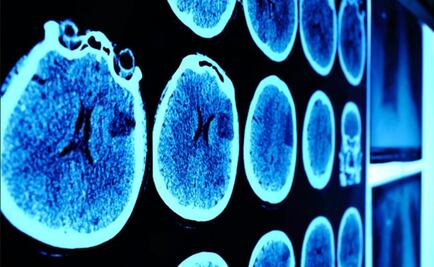

Investigadores mexicanos en conjunto con científicos de la Universidad de California Riverside desarrollaron el implante, llamado Ventana al Cerebro, que permite la utilización de rayos láser o ultrasonido como tratamiento para enfermedades que afectan al encéfalo

El objetivo es difundir el trabajo de investigadores mexicanos sobre enfermedades como Alzheimer, Parkinson y Huntington

Aunque ambas enfermedades atacan áreas diferentes del cerebro y tienen manifestaciones distintas, presentan una relación que podría llevar al desarrollo de nuevos medicamentos